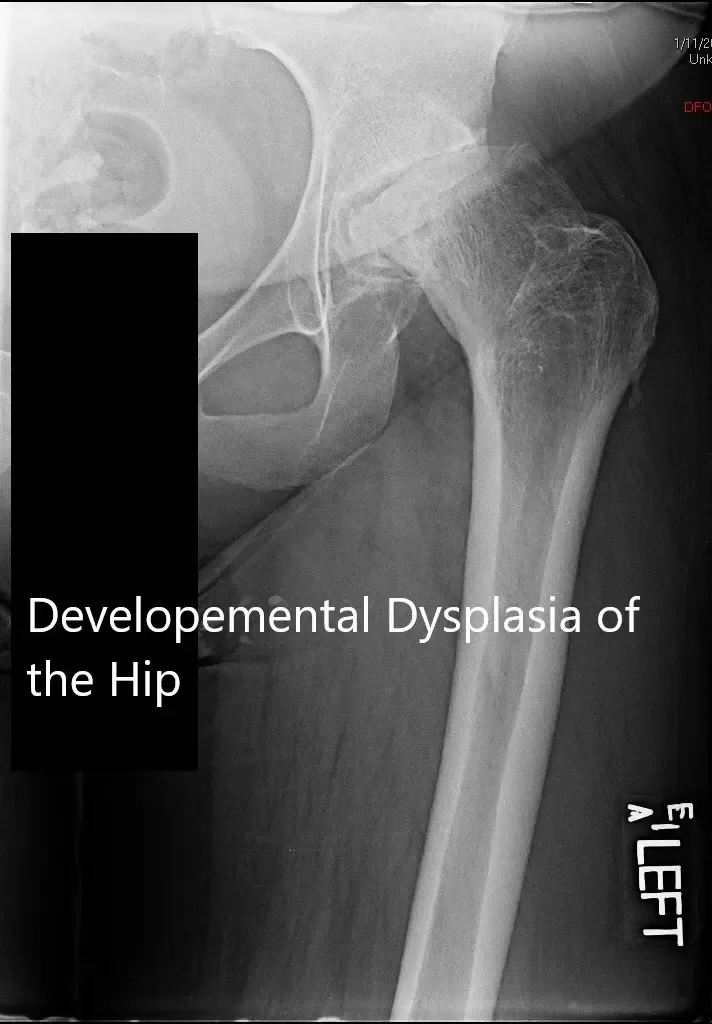

Radiografía que muestra la PA y una vista lateral limitada de la cadera izquierda

Las imágenes revelaron cambios degenerativos severos en la cadera izquierda. Hubo un estrechamiento severo del espacio articular, deformidad del acetábulo y la cabeza femoral, esclerosis subcondral y formación de osteófitos.